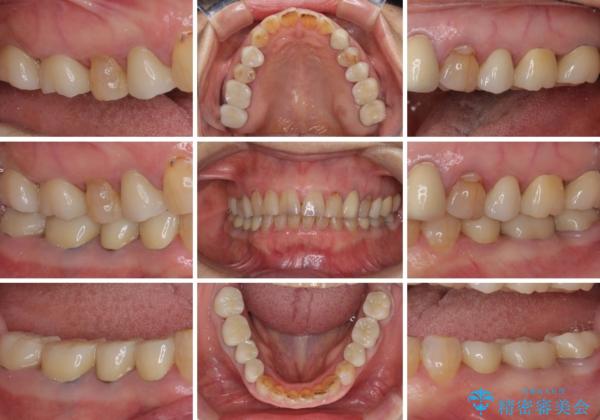

全ての奥歯の銀歯をセラミックに メタルフリー治療

土台に含まれている金属も含め、奥歯の金属は全て除去し、オールセラミッククラウンやセラミックインレーにて治療することとしました。

途中体調を崩されてしまい、その間に仮歯が外れてしまうなど、治療期間が長引いてしまいました。

治療期間はかかってしまいましたが、念願のメタルフリーとなり、患者様には大変満足していただきました。